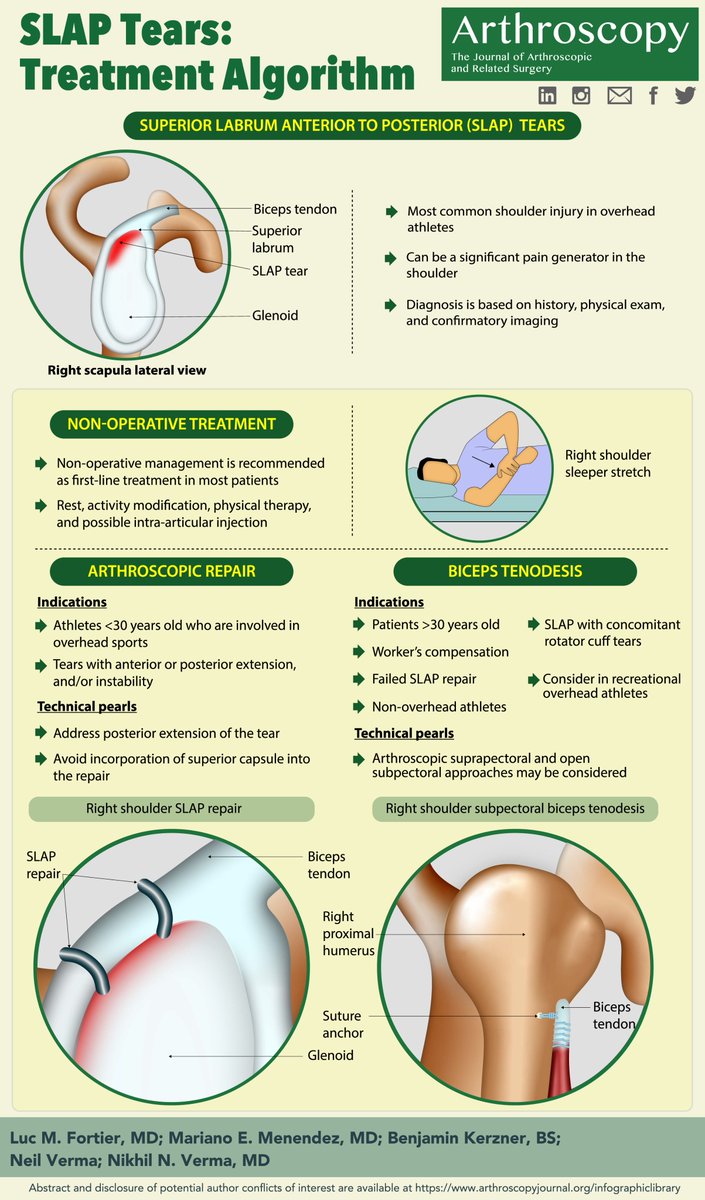

The December Infographic! SLAP Tears: Treatment Algorithm arthroscopyjournal.org/article/S0749-… Midwest Orthopaedics at Rush Mariano E. Menendez, MD